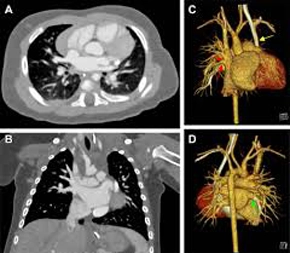

Anatomy and Pathology by CT

- Focuses on detailed visualization of normal cardiac anatomy using CT scans.

- Covers identification of all four chambers, coronary arteries and branches, cardiac veins, pericardium, and great vessels.

- Transitions to recognizing various cardiac pathologies on CT images.

- Includes the appearance of coronary artery disease (stenosis, calcification, stents, bypass grafts).

- Covers different types of cardiomyopathies (hypertrophic, dilated, restrictive).

- Includes congenital heart defects and valvular heart disease.

- Covers cardiac masses and tumors, and pericardial diseases.

- Emphasizes understanding the characteristic CT features of each condition.

- Aims to enable differentiation between normal and abnormal cardiac CT findings.

Post-Processing and Interpretation

- Equips you with skills to manipulate and analyze raw CT data for clinical information.

- Covers post-processing techniques: multiplanar reconstructions (MPR), maximum intensity projections (MIP), and volume rendering.

- Guides you through a systematic approach to interpreting cardiac CT images.

- Includes assessing image quality and identifying normal and abnormal findings.

- Covers quantifying coronary artery stenosis and evaluating cardiac function.

- Includes recognizing incidental findings.